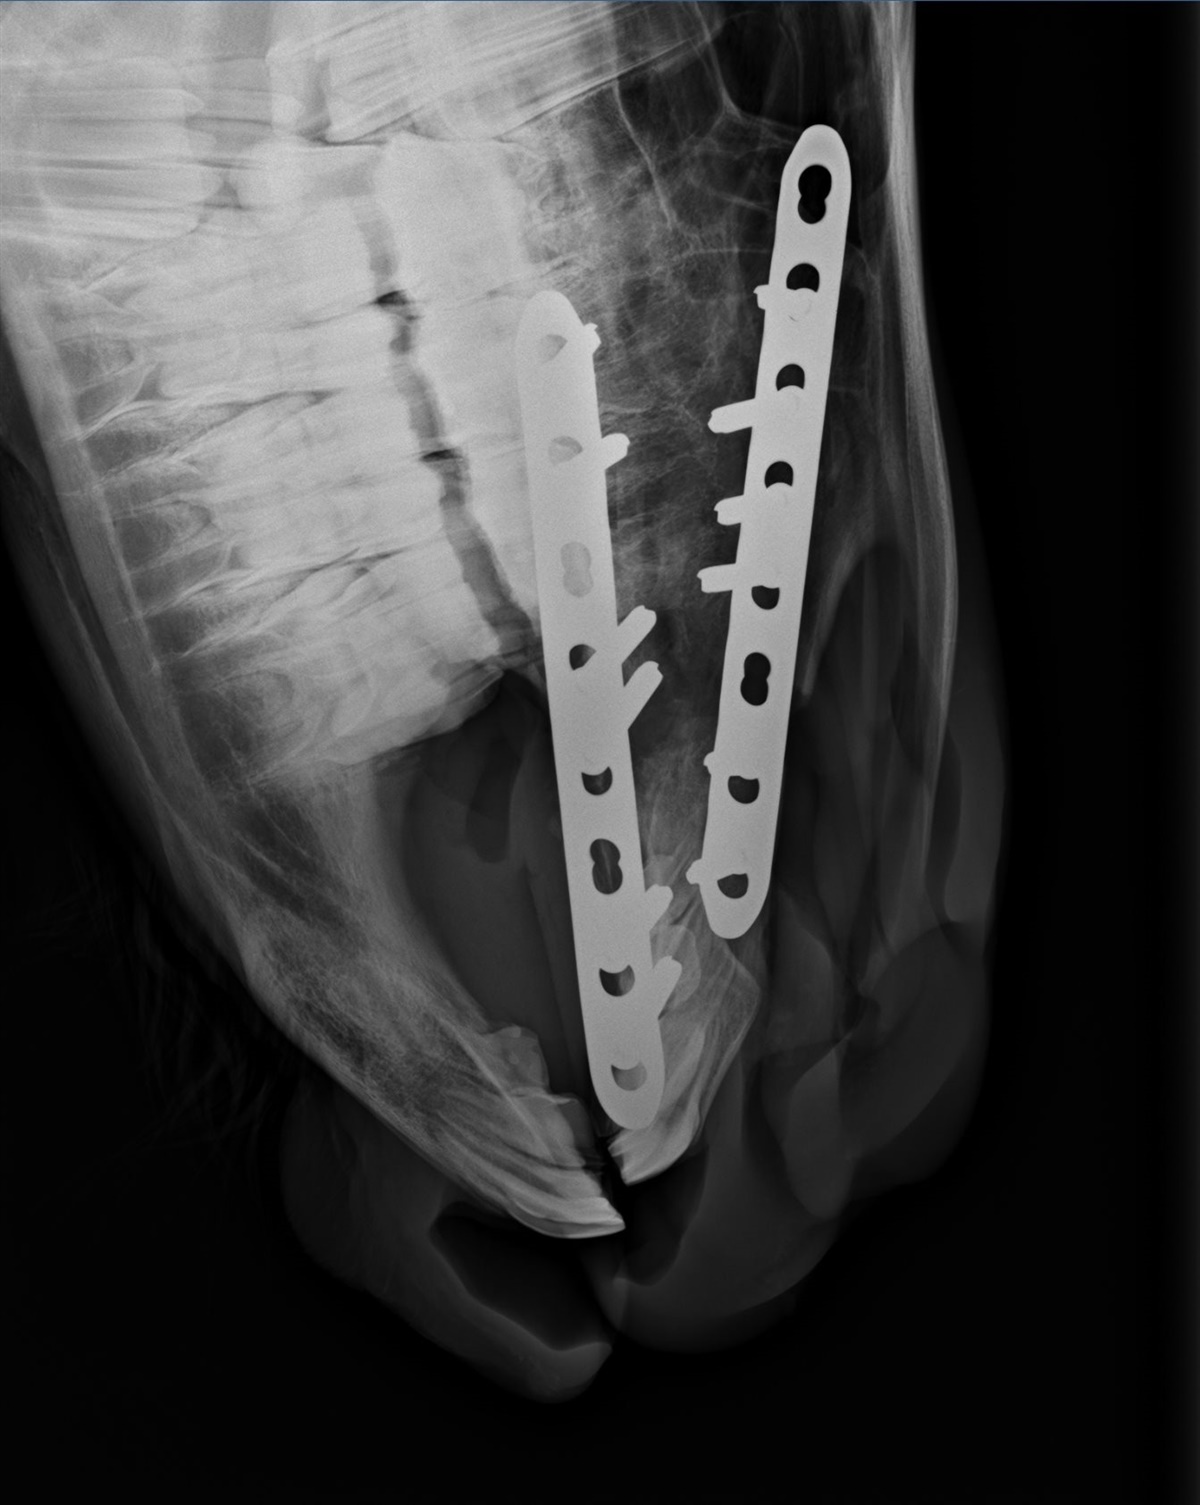

Christina ved ikke præcis hvad dyrlægerne har gjort, men Viljas mule er blevet rettet op, og hun står pt. med skinner og skruer, som skal holde det hele på plads.

– Hun både spiser og drikker fint, og virker ved godt mod. I mandags tog de kontrolrøngten af hende, og hun er ikke særlig hævet efter operationen. Hun virker heller ikke irriteret af skinnerne som sidder på siden af kæberne. Dyrlægen er godt tilfreds med operationen og måden hun takler det hele på, slutter Christina, som desuden fortæller, at Vilja skal blive hos hende.